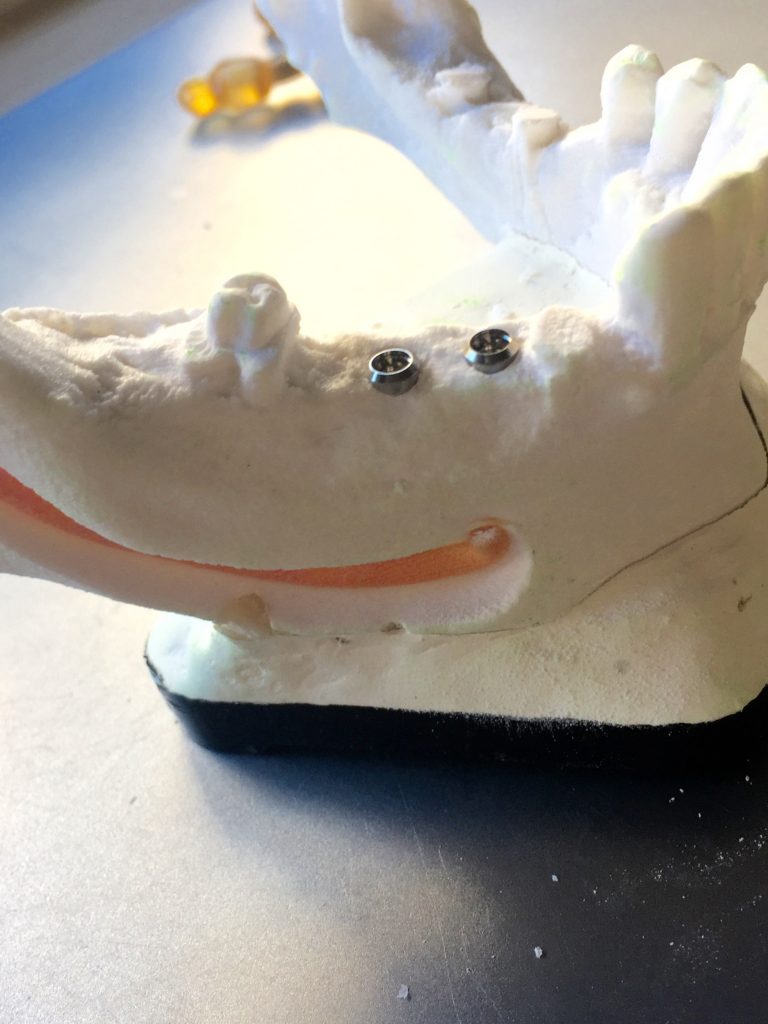

Autores: PRÓLOGO Asimismo, desde el punto de vista pedagógico, el profesional nobel en la materia tiene a su alcance la posibilidad de corregir cualquier posición implantaría en el ordenador, planear los provisionales y plasmarlos en la bio réplica antes de tocar al paciente a operar. Todos estos razonamientos nos llevan a presentar un caso de condiciones muy favorables para poner en práctica estos métodos como primer acercamiento a una Odontología Digital de alta calidad, con medios informáticos, que ya están presentes en la profesión de hoy en día, y será la protagonista única del futuro. Por otro lado, después de numerosos estudios que nos llevan a plantear el “gap” entre implante y pilar(abuttment), como principal responsable de la periimplantitis dado que la microbiota presente en el mismo es imposible de limpiar y en su presencia la cortical ósea reacciona reabsorbiéndose, nos ha llevado a utilizar implantes monobloc ya que los ejes implantarios y protéticos coincidían, y nos permitían su uso. Además, el circonio, ha mostrado a la luz de estudios muy recientes, una preservación y adhesión de los tejidos blandos superiores al titanio, tanto en su tratamiento de superficie de la rosca como a nivel gingival. DESARROLLO Paciente varón de 68 años, con antecedentes de radio/quimioterapia cinco años antes, con Rehabilitación Oral de los cuatro cuadrantes, con una Oclusión Mutuamente Compartida conservada, (REF.8) la que fracasa en el cuadrante 4, 19 años después. El mismo presentaba un puente de porcelana sobre circonio con pilares en 44 y 47, reemplazando el edentulismo de 45 y 46. Se produce la fractura del PM del 44, y ante una endodoncia antigua y corta, se decide implantar las zonas edéntulas, conservando temporariamente los pilares, hasta producida la oseointegración, para entonces también exodonciar el 44. DIAGNÓSTICO Tomamos impresiones del maxilar antagonista, Arco Facial Estático y realizamos montaje del mismo mediante la sistemática ARTEX. Producimos la relajación del músculo Pterigoideo Externo, para obtener la ORC (Oclusión en Relación Céntrica) mediante el método de Laminillas de Long, basado en el concepto de INERVACIÓN RECÍPROCA. Esto nos permitirá montar el maxilar inferior, tanto en su forma de: La primera para practicar la cirugía guiada y comprobar su eficacia, y el modelo de yeso para ser escaneado y confeccionar la GUÍA QUIRÚRGICA. La Biorréplica la obtenemos transformando los archivos DICOM que nos da el CBCT en archivos STL, y a partir de ellos, mediante una tecnología de PROTOTIPADO RÁPIDO, la obtención de un objeto físico en 3D a través de la aglutinación selectiva de una sucesión de capas de polvo. Procedemos a montar la biorrèplica y el modelo de yeso del caso. Podemos verificar la exactitud de las medidas del hueso residual en la bio réplica y compararlas con el scanner. Arrojando un resultado de 8,5 mm de cortical externa a cortical externa. Pudiendo también medir la distancia hasta el dentario. y comparar gracias a la ventana lateral de la biorréplica Dándonos 22mm de distancia. Con lo cual deducimos que implantes de 4,1mm por 12 mm serán perfectamente rodeados de hueso. Medimos también la distancia desde oclusal del antagonista, hasta el hueso desnudo. Lo mismo que, mediante la utilización de la guía radiológica, con un material radiolúcido colocado en gingival de la misma, podemos medir la altura de la encía. Con lo cual podemos calcular la altura del pilar. Es entonces cuando con el programa COC Diagnostix se realiza la programación final: Obteniendo no solo la ubicación, largo, ancho y ángulo de los implantes sino también los provisionales mediante CAD CAM. Ya entonces podemos hacer la práctica quirúrgica en la bio réplica, mediante la guía quirúrgica, instalando los implantes de prueba que no serán los de circonio, ya que la casa no cuenta con ellos, pero si otros de las mismas dimensiones. TRATAMIENTO Entramos ya en la cirugía propiamente dicha. Antisepsia de la zona a operar y zonas anexas. Comprobación del perfecto ajuste e inmovilidad de la G.Q. en boca durante la cirugía. Marcado de la encía y perforación de la cortical. Visión a través de la Guía de la mínima intervención anterior. Comprobación sin Guía. Incisión mínima mesio distal, para apartar y conservar encía queratinizada. Secuencia de drills, perforando a profundidad requerida Observación del Mínimo Trauma Implantes Strauman de Zirconio Monoblock en blíster y montádo en contrángulo reductor. Instalación controlando torque con contrángulo reductor. Comprobación clínica. Comprobación Radiográfica y con Guía. Toma de impresiones, y armado de modelos con técnicas de pasividad protética. Montaje. Resultado de las provisionales ejecutadas por CAD CAM Al no estar conformes con el resultado decidimos desechar dichas provisorias y optar por repetirlas. Nuevas provisorias realizadas mediante encerado convencional. Estado de los tejidos blandos. Provisorias en boca. Oclusión de Estímulo Inmediato. Ref.10: Carga inmediata .Alberto y Diego Bechelli. Comprobación mediante CBCT post operatorio Componentes del equipo (En la próxima presentación, mostraremos las coronas definitivas de porcelana sobre circonio, y la desoclusión provocada por una OCLUSIÓN MUTUAMENTE COMPARTIDA, sobre estos implantes y otros seis mas) REFERENCIAS

A-BIORRÉPLICA

B-MODELO DE YESO

FIG: 14-15-16-17-18-19-20

FIG: 21-22-23-24-25-26

Mas adelante, y por cuestiones de conveniencia protética, el implante instalado del premolar será de 3,3 mm.